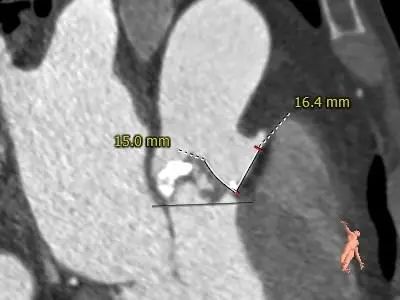

LEFT CORONARY

RIGHT CORONARY

LCA&LEAFLET

RCA&LEAFLET